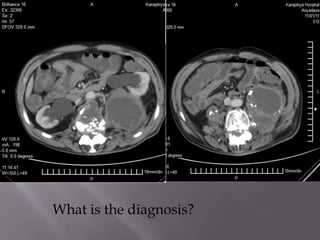

What is the diagnosis?

DIAGNOSIS;

TUBERCULOUS SPONDYLITIS WITH

BILATERAL CALCIFIED PSOAS ABSCESSES

AND BILATERAL HYDRONEPHROSIS.